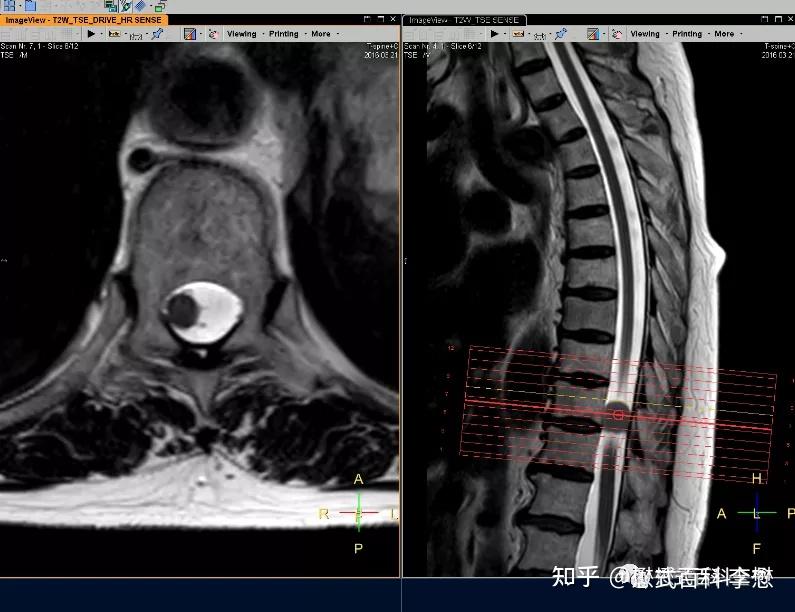

磁共振脊柱规范扫描及技术应用(胸椎部分) - 知乎

图片尺寸795x612

图片尺寸830x596